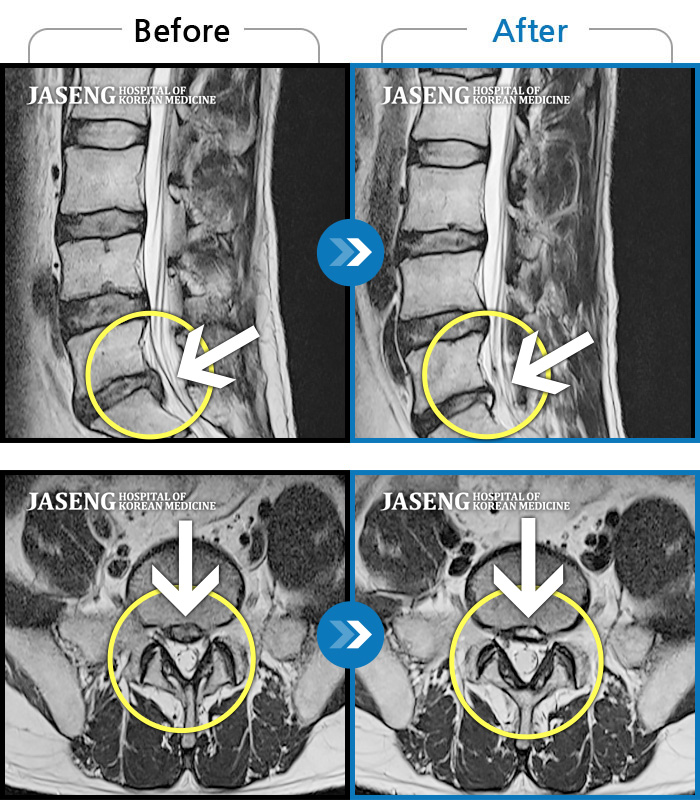

Before

After

환자에게 사전 동의를 받아 동일 조건에서 촬영되었습니다.

개인에 따라 치료 후 부작용이 발생할 수 있으니 의료진과 상담 후 치료를 진행하시기 바랍니다.

허리 아프고 보행시 우측 다리 통증

하부요추와 좌측 하지 후면 통증, 좌측하지 감각저하, 근력저하